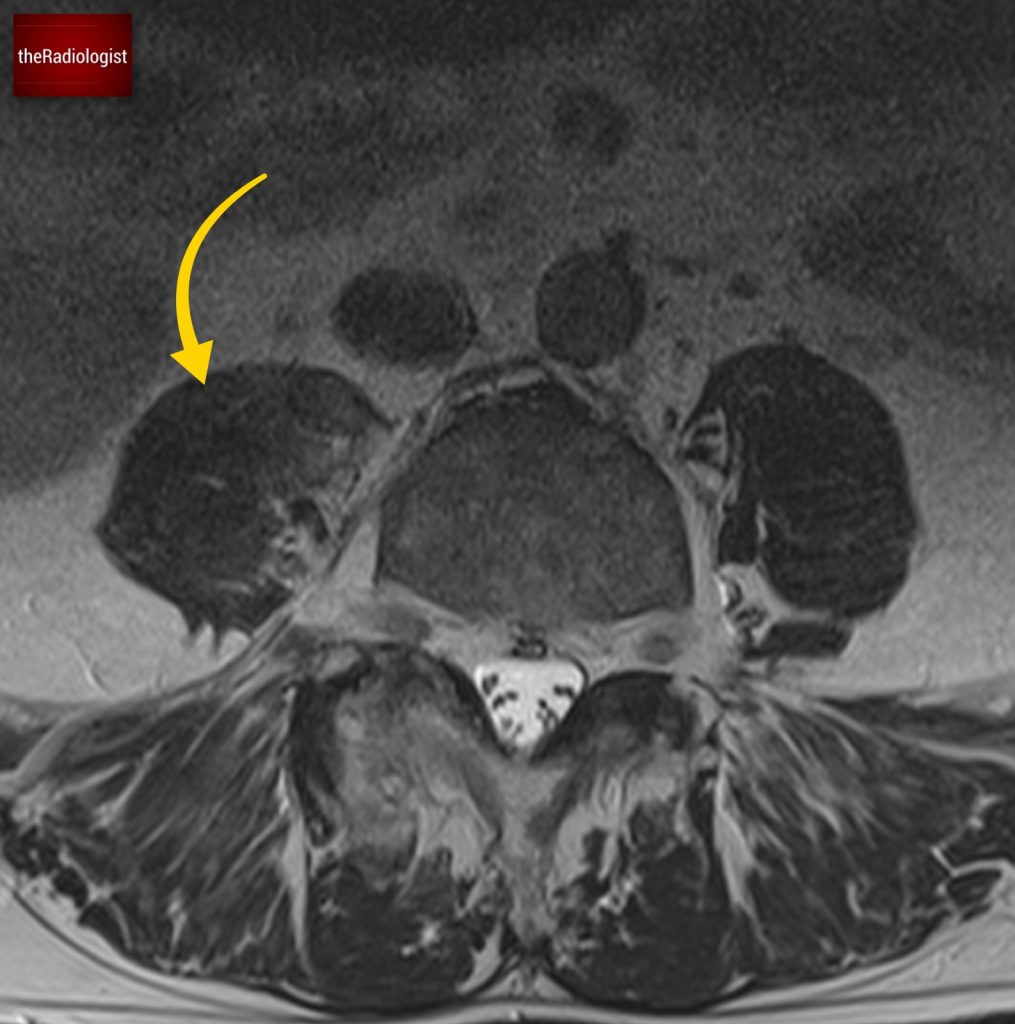

Due to pain the patient could only tolerate a few STIR sequences so we don’t have a complete scan but have a look at this axial STIR sequence below. We have high STIR signal within the right psoas with locules suggesting abscess formation.

Have a look at this axial STIR image from the MRI scan. Here we have high SITR signal within the right psoas with locules suggesting abscess formation.